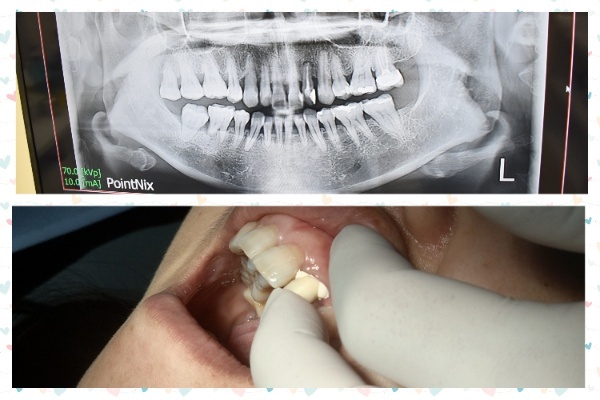

第一次看診會做洗牙和斷層掃描

這過程中楊策淳院長也會說明全瓷冠假牙製作步驟跟注意事項

製作假牙前楊院長會將牙齒磨小

接著會做一個取模動作

取模時會有些不太舒服需要稍微忍耐3-5分鐘左右

因為側門牙已經被研磨變小

所以楊院長有製作一個臨時假牙套上做覆蓋

楊院長會將做好的假牙使用臨時黏著劑先黏附在側門牙上

試戴假牙時楊院長會反覆拿一張紅色拭紙放在牙跟牙咬合面做測試

太高或是感到不舒服的地方楊院長就會幫忙取下處理